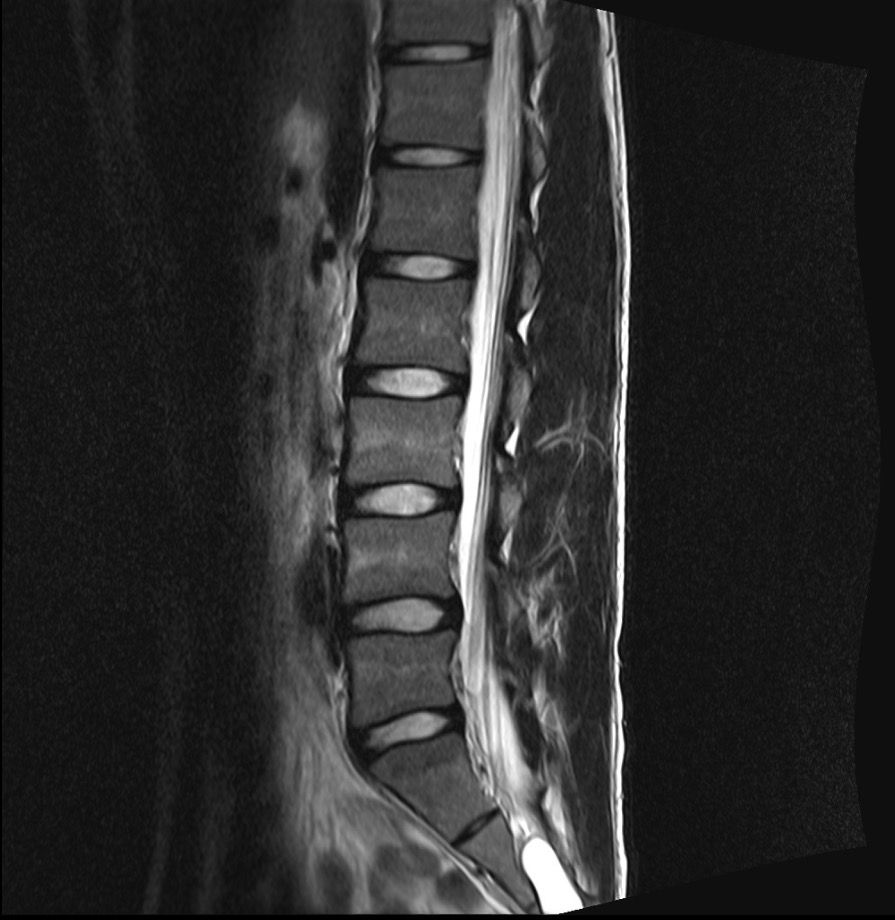

Mrl 보시고 확인좀 부탁드리겠습니다 교통사고가 나서 허리가 안좋아서 Mrl 촬영했습니다 근데 디스크가 있다고 합니다 한방병원에서는 있다고 하고

허리전문병원에서는 없다고 합니다

mri상으로볼때에는 디스크가 약간 나와있는걸로보이지만 신경을 자극한다거나 다른문제는없어보이는데요 일단 불편감이지속되고있다면 근육의긴장이나 염증으로인해서 그러는증상일수도있습니다

신경 압박이나 심한 병변이 없으면 허리 전문 병원에서 문제 없다고 판단할 수 있습니다. 한방병원은 미세한 변화도 디스크 문제로 볼 수 있어 의견 차이가 생길 수 있습니다.

올려주신 사진상에서 허리 아래부위에 존재하는 디스크가 약간의 돌출이 보이는데요, 신경을 압박하는 것처럼 보이지는 않습니다.

디스크 돌출이나 경미한 추간판 탈출증으로 보이는데요, 각 병원에서 견해에 따라 허리디스크로 진단하거나 하지 않는 것으로 보입니다.